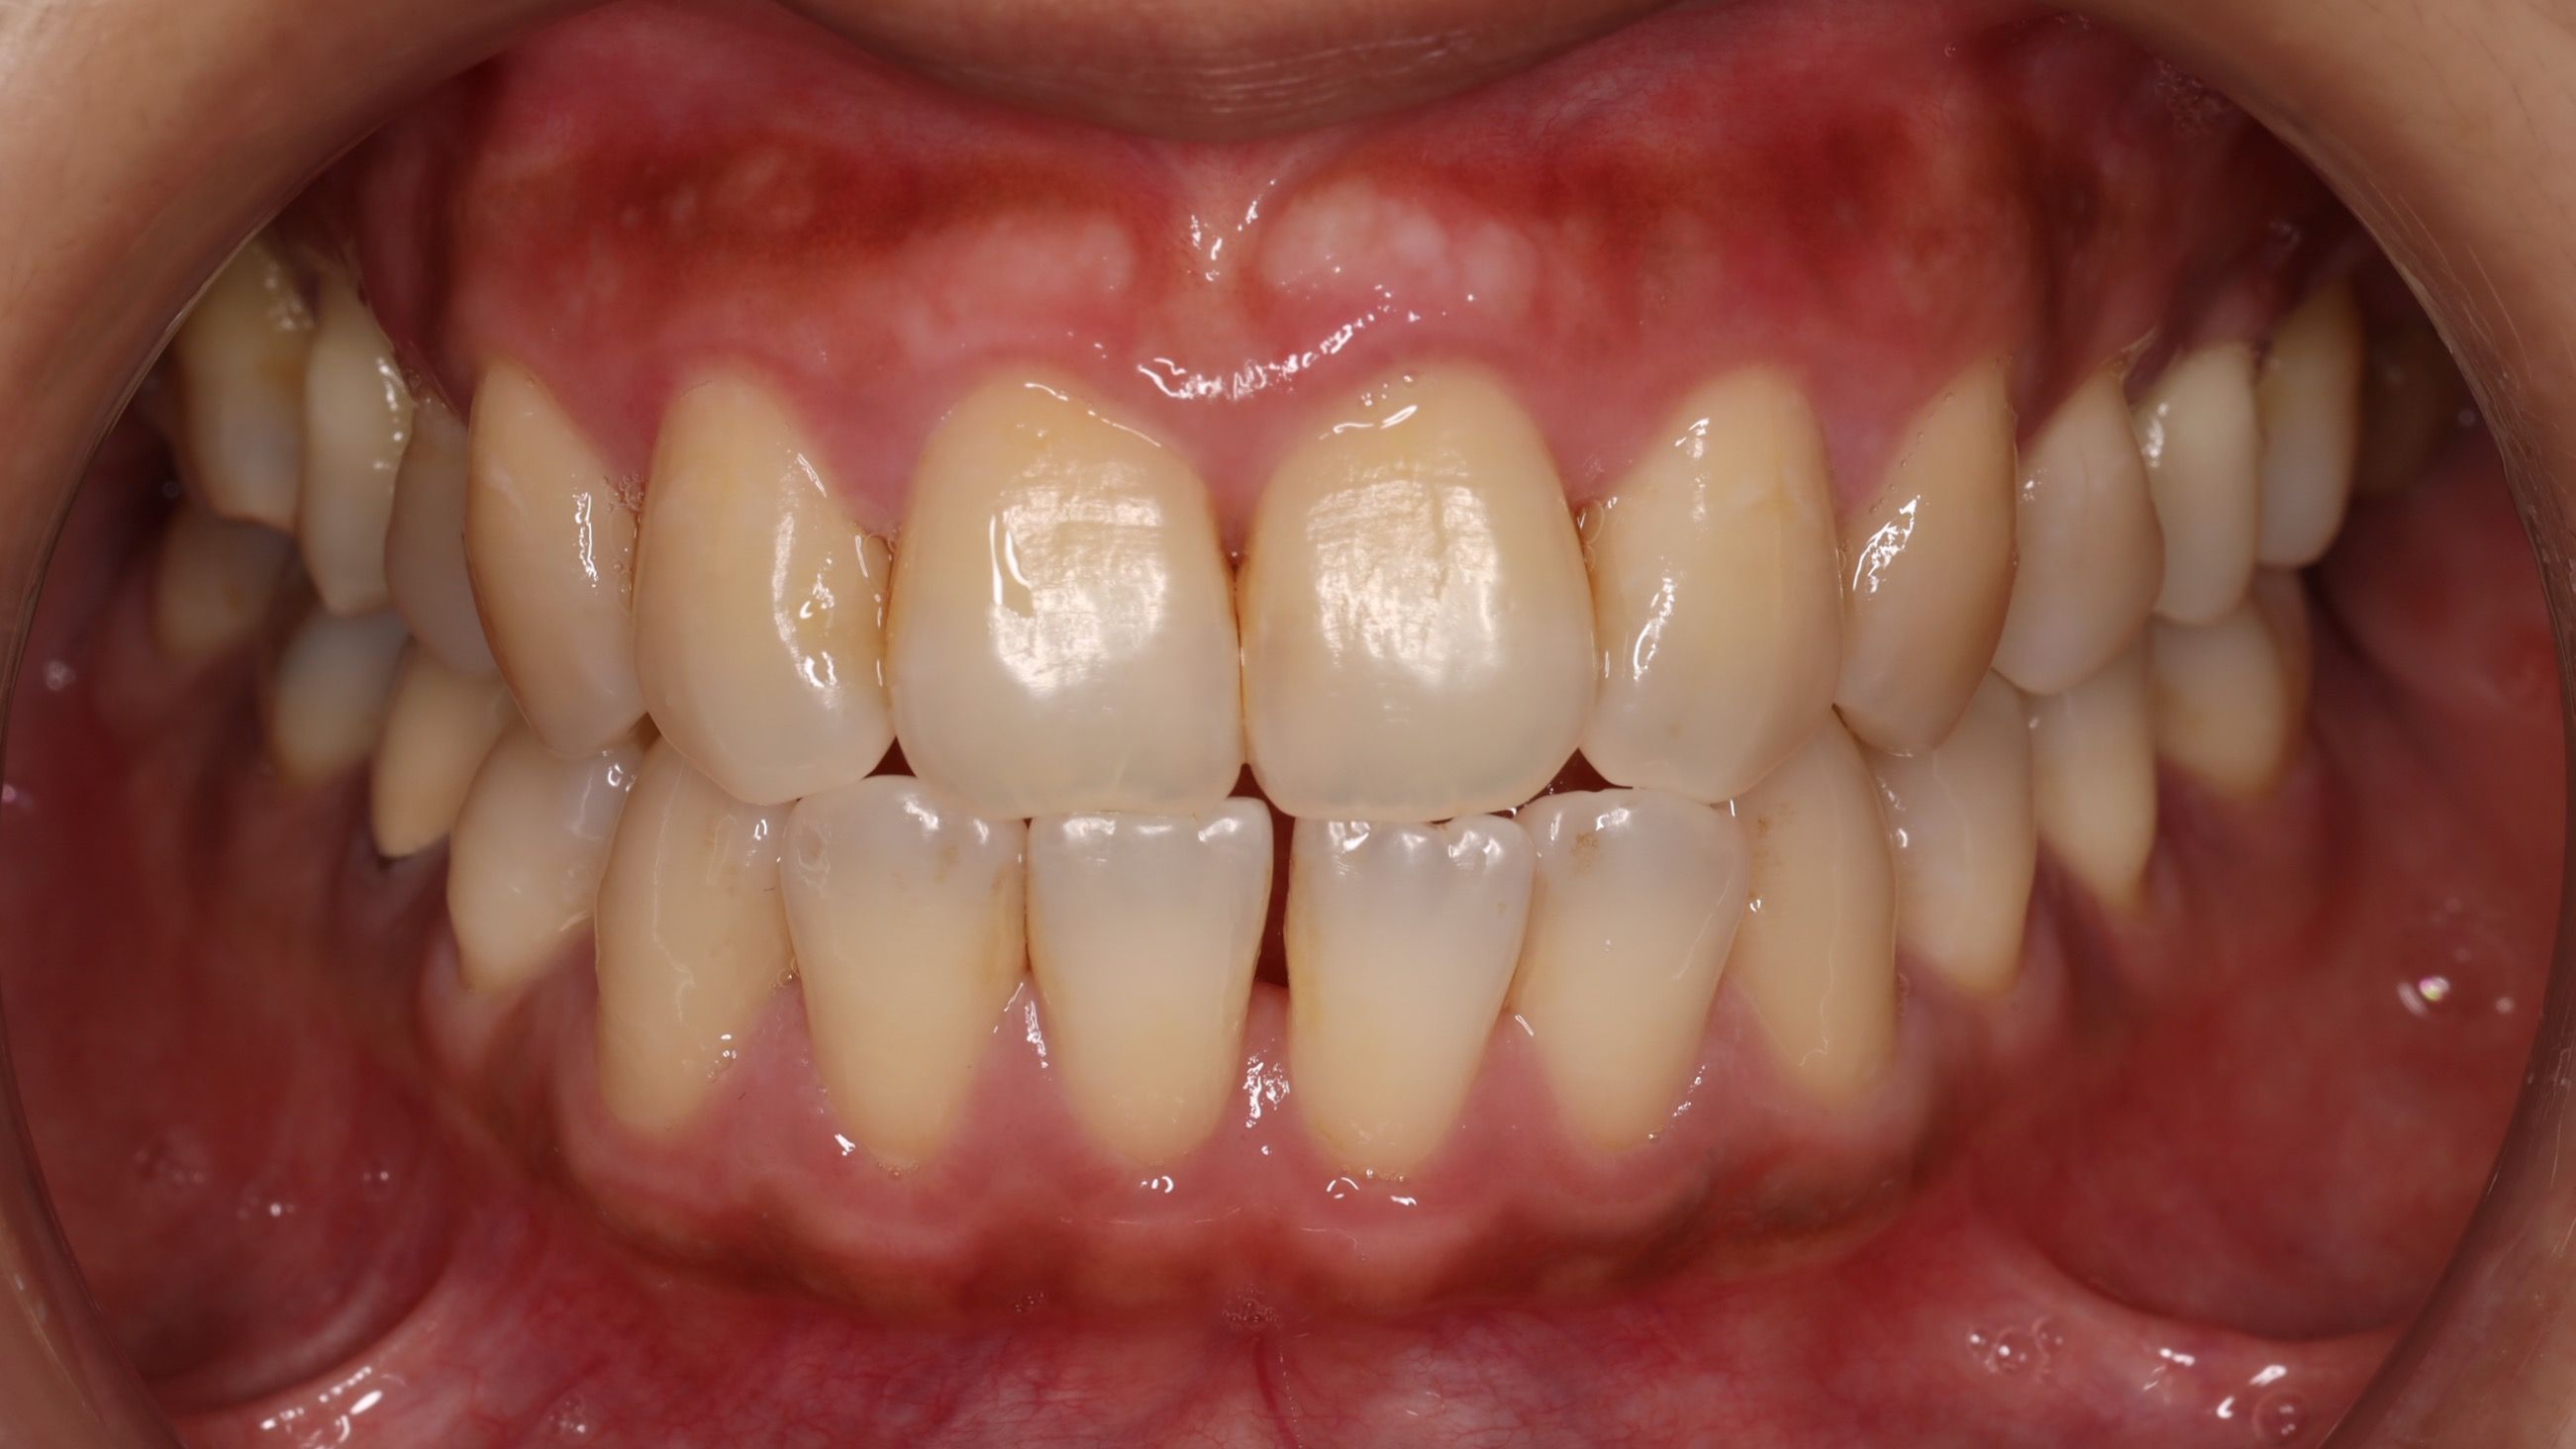

古小姐第一次來到診間時,主要是希望能做全口的詳細評估與檢查,因為她進食較黏稠的食物,牙齒容易感到疼痛,刷牙的時候容易出血,更令她困擾的問題是,她以前因為蛀牙拔掉牙齒,但沒有進行後續處理,左下方有缺牙的情況,除了導致牙齒開始出現縫隙,長期習慣用右邊進食,也讓她兩邊咬合都不太舒服。

咬合與牙縫問題 - 影響整體美觀與功能

第三階段:重建牙齒正常排列&空間

等到牙齦狀況穩定後,開始約一年的隱適美療程。矯正過程不只是要關閉牙縫,更重要的是要調整牙齒的角度和位置。由於缺牙時間過久,導致上方對咬牙失去抗衡,隨時間逐漸往下掉,因此也需要藉由矯正的力量把它們推回正確的位置。